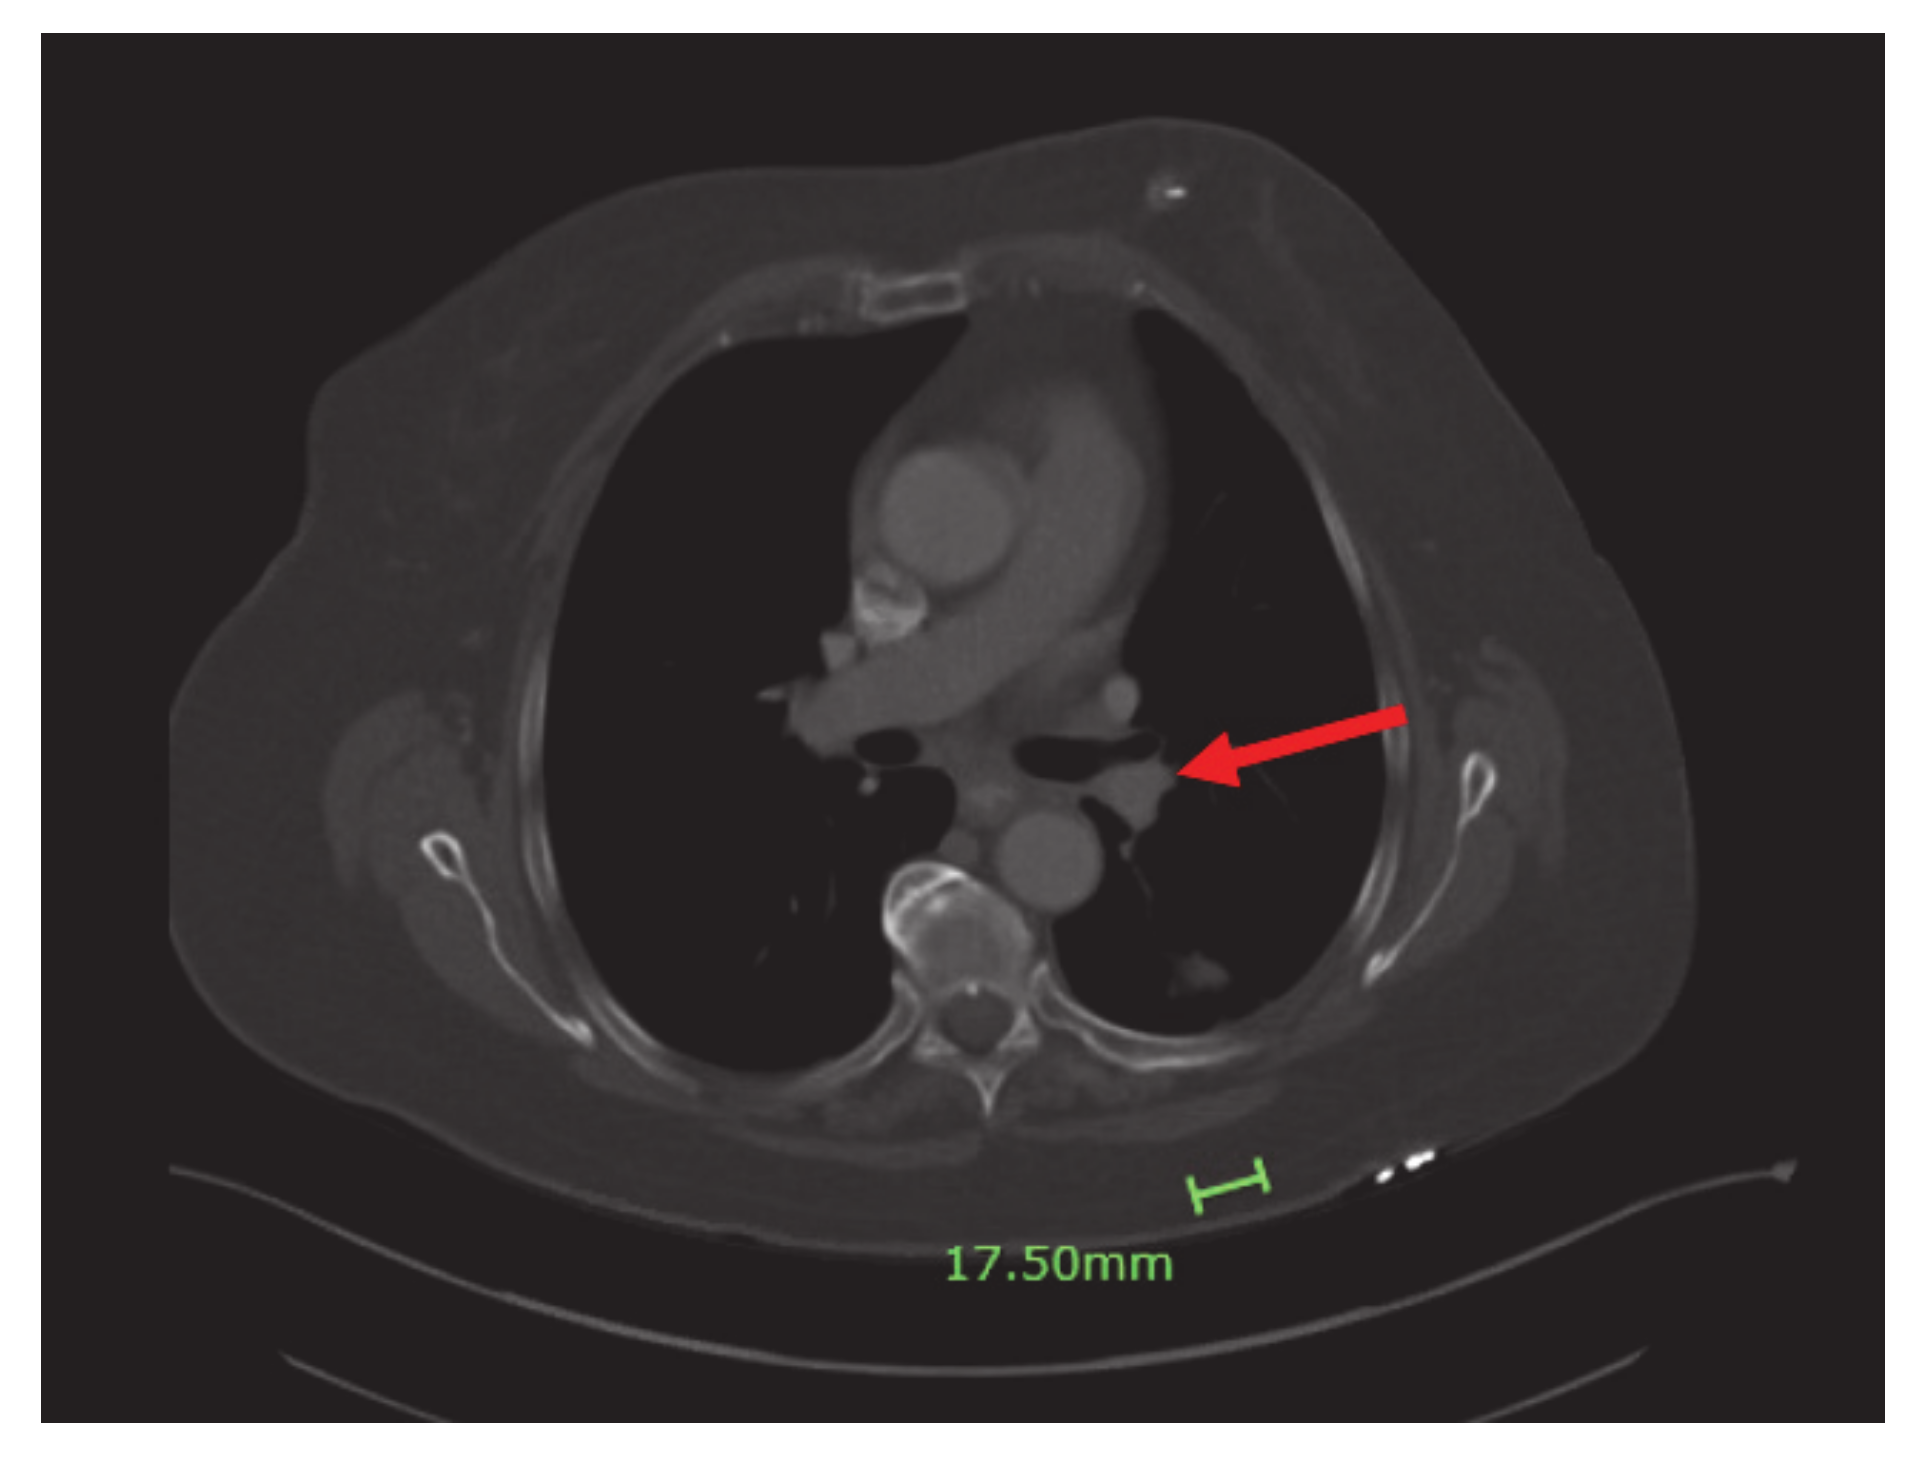

A 75-year-old non-smoker female with personal history of estrogen receptor (ER), progesterone receptor (PR) positive, Her2/neu negative breast cancer diagnosed 14 years ago, status post left breast lumpectomy, radiation, and 5 years of anastrozole with no evidence of recurrence, initially presented in early February 2020 for symptoms of persistent cough productive of green phlegm since January. She received azithromycin and prednisone for presumed pneumonia without improvement of symptoms. Later, she received levofloxacin and was referred to pulmonology for further evaluation. Computer tomography (CT) scan at that time showed left lower lobe consolidation/atelectasis with obscuration of proximal left lower lobe bronchus as well as mildly enlarged mediastinal nodes, concerning for underlying peribronchial lesion (Figure 1).

Figure 1.

CT chest: left lower lobe consolidation/atelectasis (red arrow) with obscuration of proximal left lower lobe bronchus and mildly enlarged mediastinal nodes.